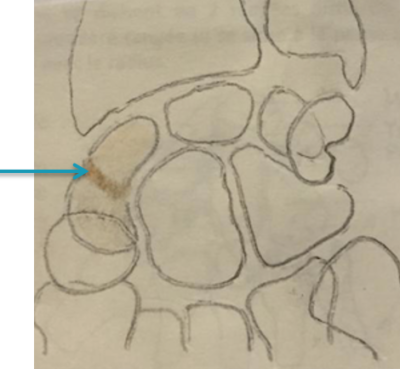

Le scaphoïde fait partie des os du carpe. Les os du carpe sont au nombre de 8 et se divisent en 2 rangées distinctes. Le scaphoïde appartient à la première rangée (il se situe à la partie la plus externe) qui est articulée avec le radius.

Radio, IRM et scanner d’une pseudarthrose du scaphoïde